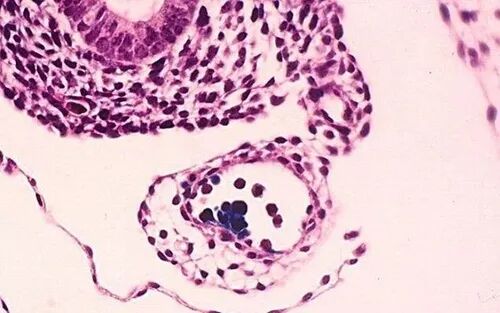

干细胞具有强大的免疫调节作用。在胰腺损伤引起的炎症反应中能够发挥强大的抗炎功能,减轻炎症损伤。干细胞能够抑制T细胞、B细胞和NK细胞的功能,也影响了树突状细胞的活性。

树突状细胞是激活初始T细胞最重要的抗原呈递细胞,干细胞能够抑制树突状细胞的迁移。抑制其成熟,进而抑制树突状细胞的抗原递呈作用,抑制T淋巴细胞的活化和增殖。